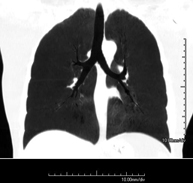

- Chest CT

Diagnostic test that provides high definition anatomical images of the chest (lungs, heart, mediastinum, great vessels, rib cage, etc.) using CT (Computed Tomography) equipment. These images are then examined on a workstation that allows bidimensional reconstructions in different planes of space and also 3D reconstructions (volumetric). Some studies require the use of an iodinated contrast agent to improve image definition.